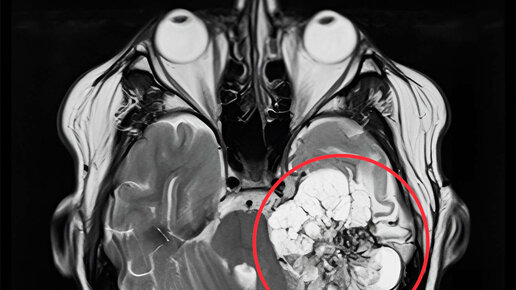

Очередная МРТ. 12.05.2023